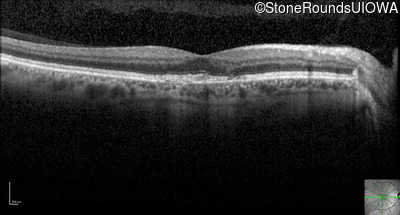

Optical Coherence Tomography - Left - 20/40 +1

Exemplar / OCT Stack